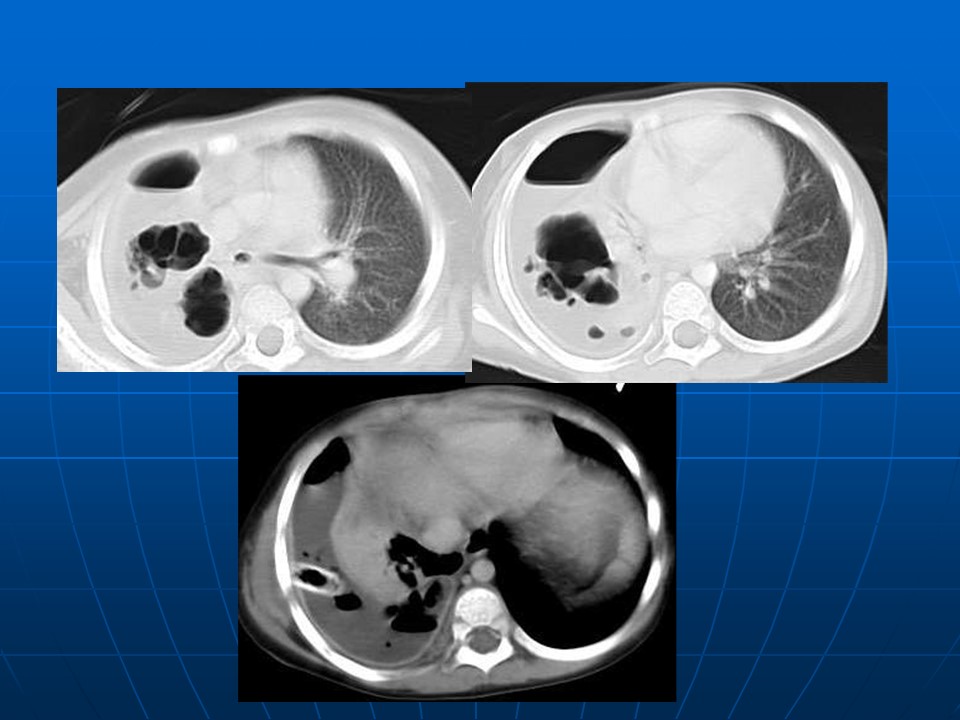

【PPT】早期肺癌易漏诊征象分析